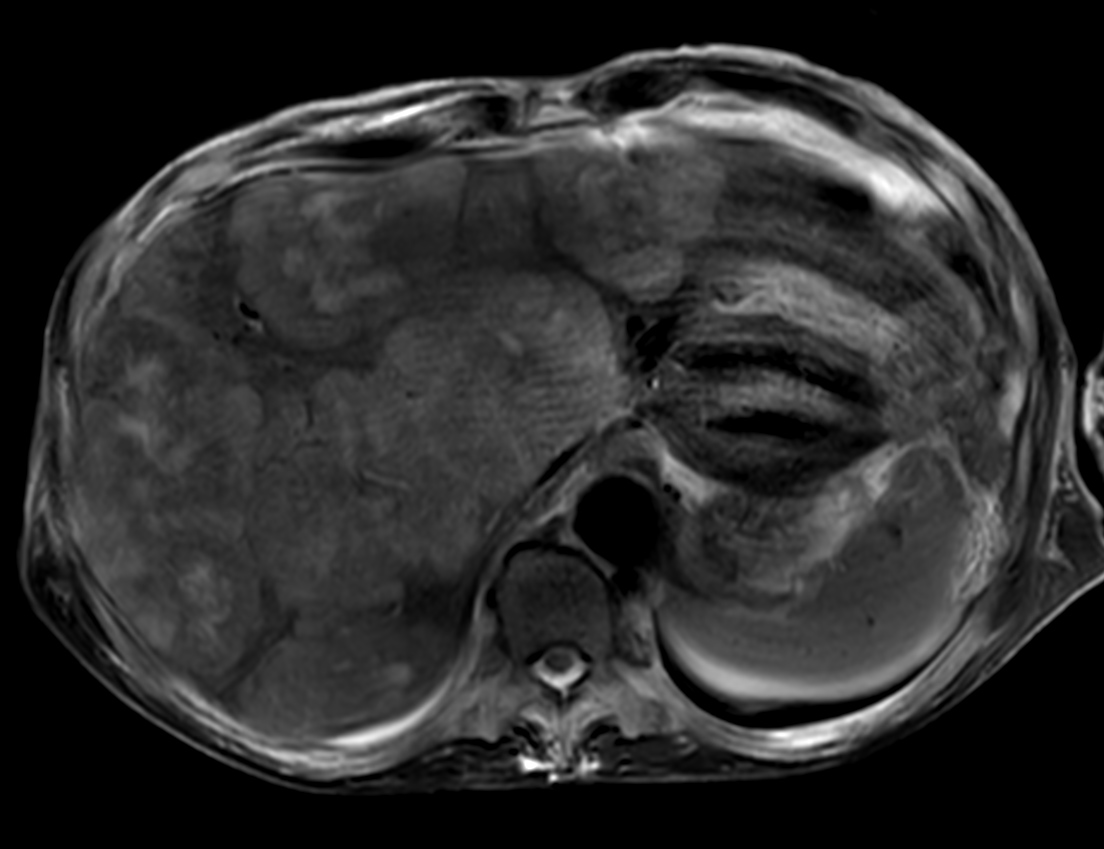

Patient with liver metastasis. The ExamCard includes techniques for efficient fat-free imaging over large field-of-views (mDIXON XD), a procedure for non-invasive liver fat quantification (mDIXON Quant), a multi-phase contrast-enhanced sequence (4D FreeBreathing) to improve imaging confidence and Compressed SENSE to accelerate the entire exam.

T2w TSE FatSat